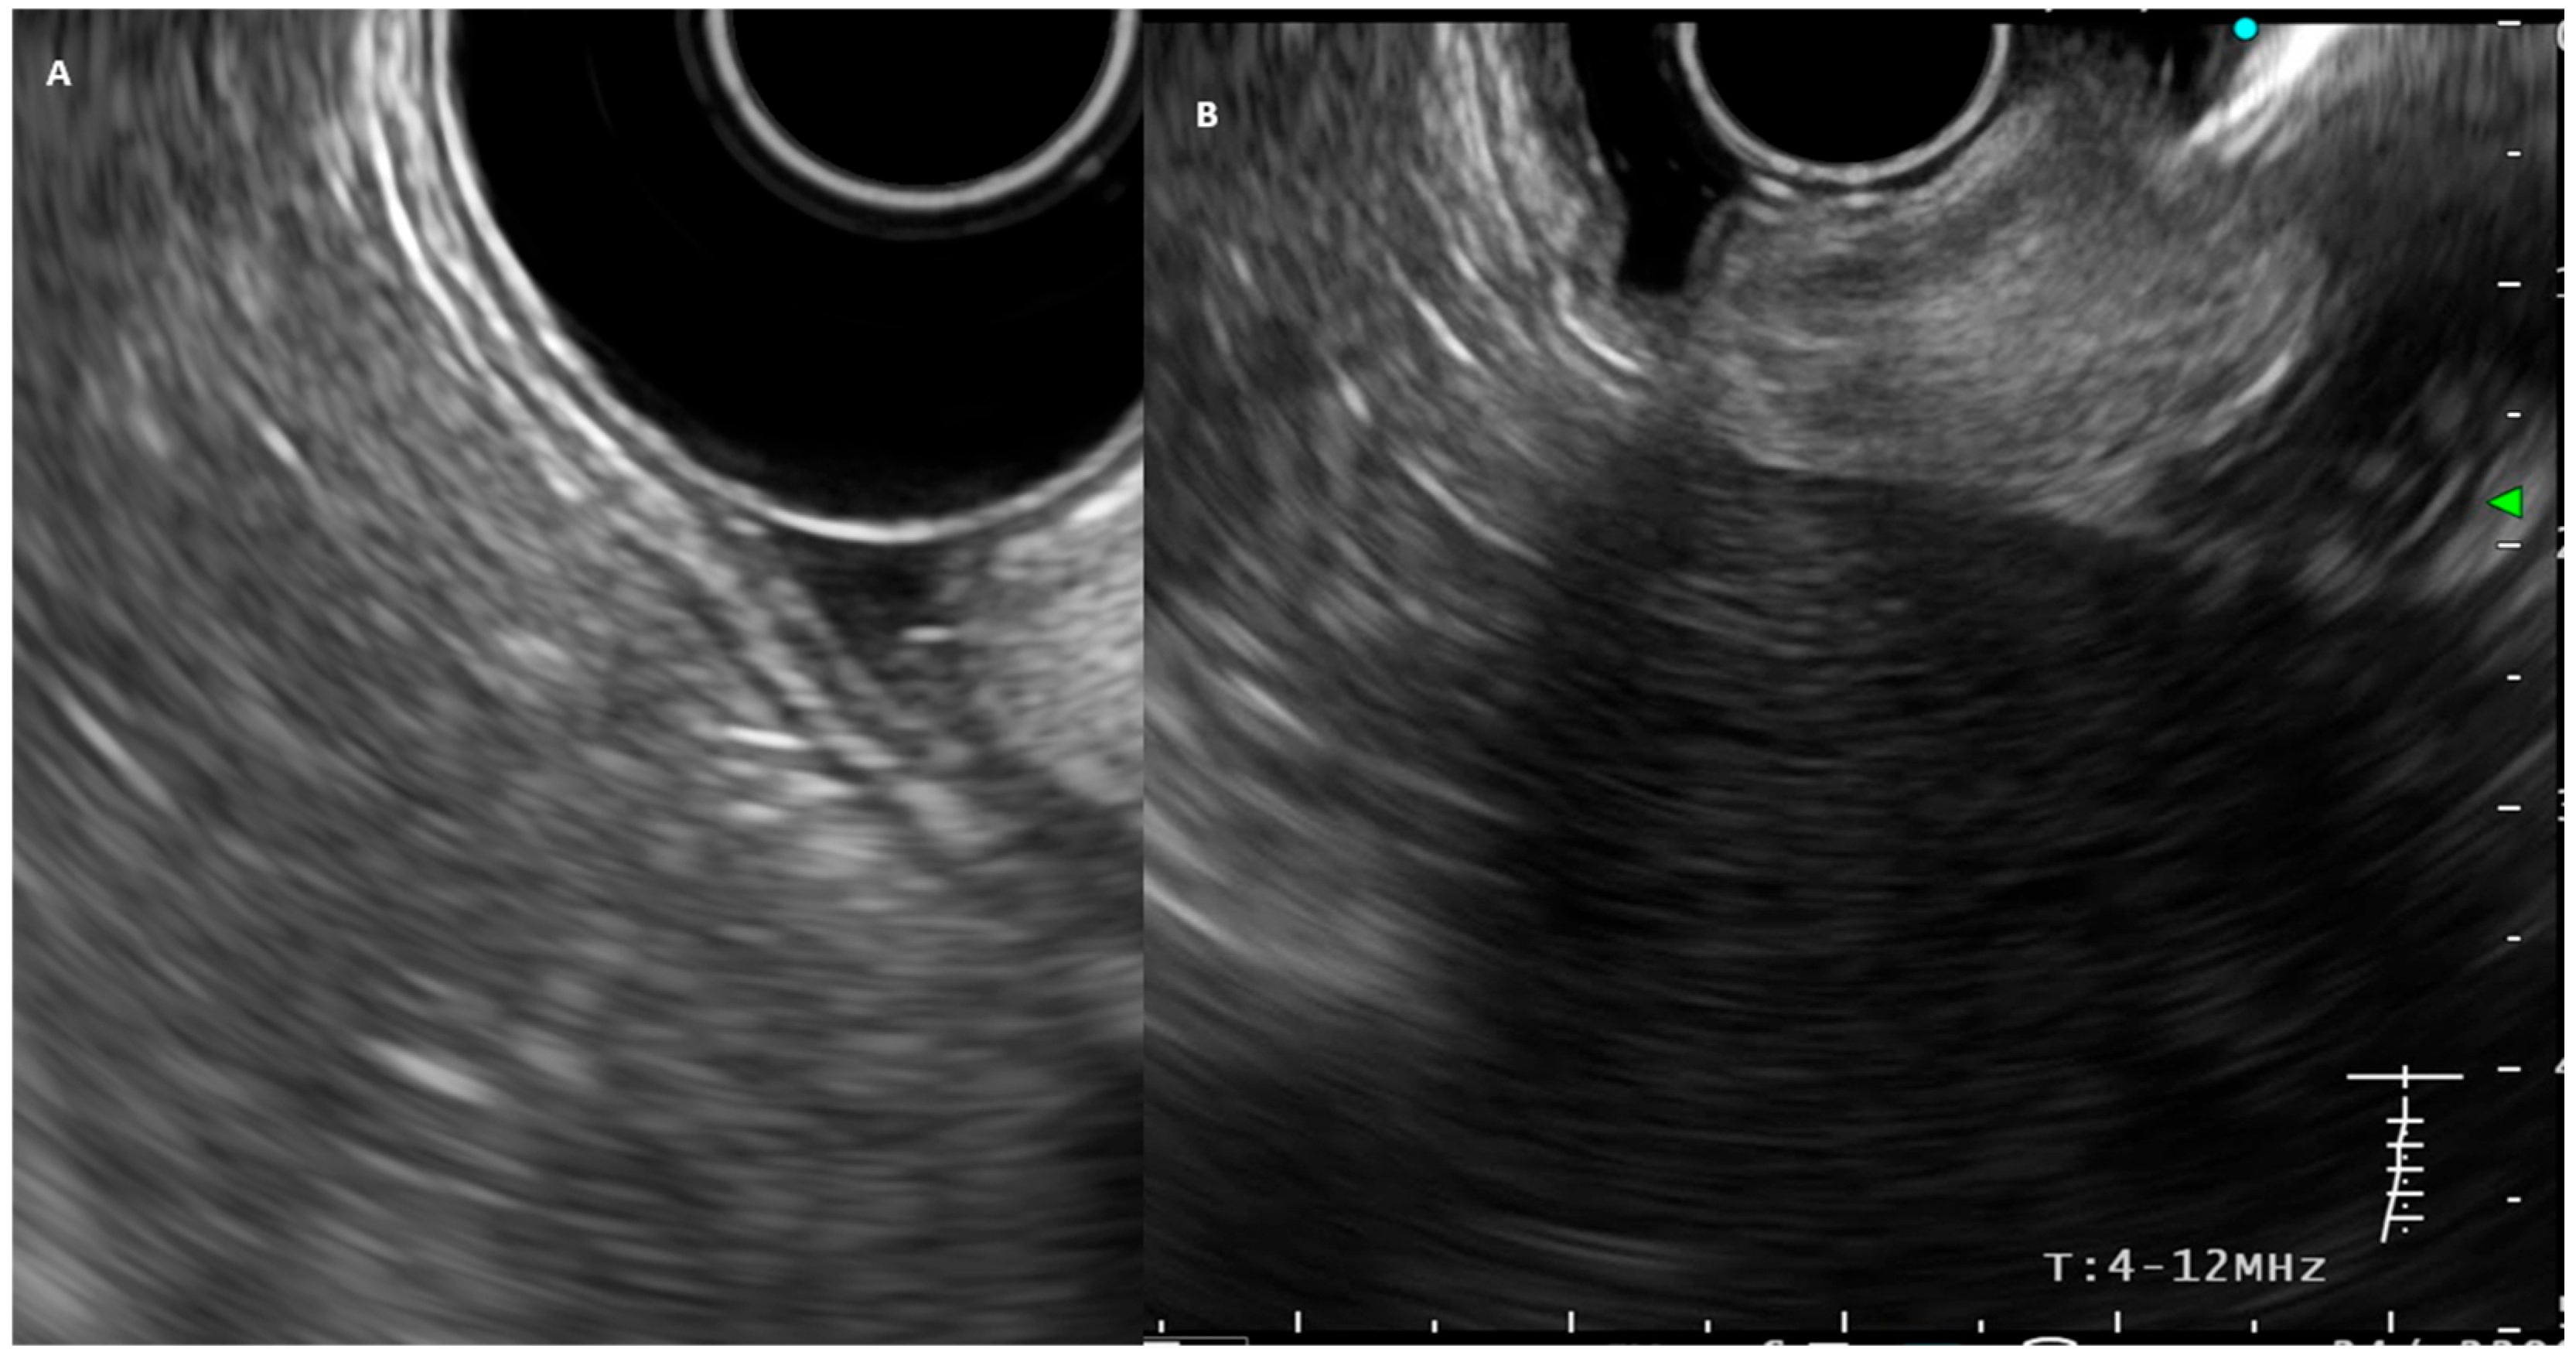

Figure 1.

(A) EUS-image of the normal gastric wall. (B) EUS image of a gastric cancer with an echo-poor tumor involving the full thickness of the gastric wall (stage T3).